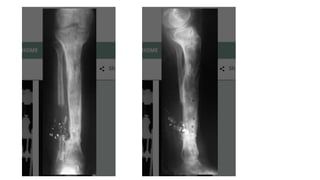

Ilizarov method

• Law of tension stress and distraction osteogenesis

• Corticotomy is done in the fracture fragments and both the fragments

are distracted.

• When the desired length is achieved, distraction is stopped and

consolidation of the new bone formed occurs

• Gold standard in infective gap non union

• Fibular osteotomy

• Removal of fixator:

Atleast three cortices should be ossified in AP and Lat view xrays

Protected weight bearing

Ilizarov method • Lawof tension stress and distraction osteogenesis • Corticotomy is done in the fracture fragments and both the fragments are distracted. • When the desired length is achieved, distraction is stopped and consolidation of the new bone formed occurs • Gold standard in infective gap non union • Fibular osteotomy

• 21.

• Removal offixator: Atleast three cortices should be ossified in AP and Lat view xrays Protected weight bearing • Advantages: no skin incision is made, minimally invasive (wires and pins) Very little soft tissue handling Can correct length and deformities in three dimensions Patient can weight bear early after application